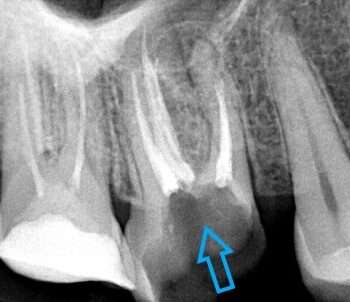

Επανάληψη απονεύρωσης σε τρία άνω πρόσθια δόντια